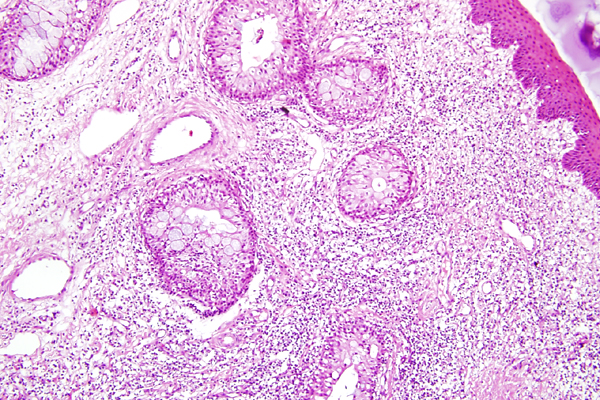

| 10x   |   Hematoxylin and Eosin | ||||

The superficial subconjunctival connective tissue is expanded by inflammatory cells.